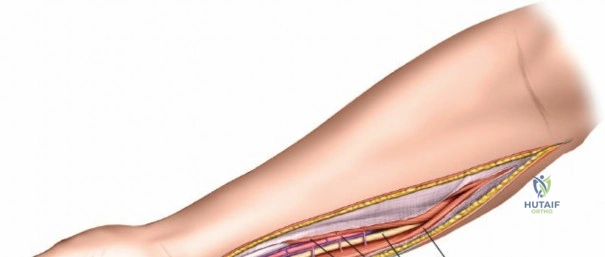

Incision: A curvilinear incision is made from the medial epicondyle, across the antecubital fossa, extending obliquely to the mid-volar aspect of the forearm, and then longitudinally down to the wrist crease, potentially extending into the palm to release the carpal tunnel. The incision should be generous, allowing for wide exposure.

- Key points: The proximal portion of the incision should curve gently to avoid crossing the elbow flexion crease at a right angle, which could lead to contracture. Distally, it should avoid cutting directly over the median nerve at the wrist.

This image shows the standard curvilinear incision for the volar approach, extending proximally from the medial epicondyle, gently crossing the antecubital fossa, and proceeding distally across the mid-forearm to the wrist.

- Key points: The proximal portion of the incision should curve gently to avoid crossing the elbow flexion crease at a right angle, which could lead to contracture. Distally, it should avoid cutting directly over the median nerve at the wrist.